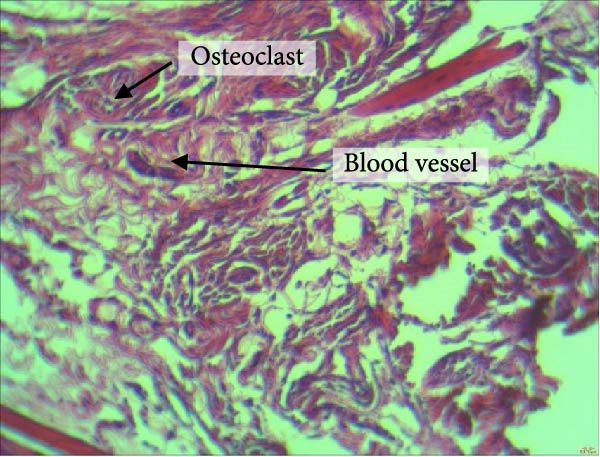

Figure 4 shows the periodontal tissue light‐microscopic findings in the study groups. As shown, the number of blood vessels, osteoclasts, and Howship’s lacunae was significantly higher in rats subjected to stress and CE injection for a 40‐day period, compared with others.

Figure 4H&E staining. Blood vessels and osteoclasts in different subgroups: (A) orthodontic treatment/CE injection/stress (chronic); (B) orthodontic treatment/CE injection/stress (acute); (C) no orthodontic treatment/CE injection/stress (chronic); (D) no orthodontic treatment/CE injection/stress (acute).(A)(B)(C)(D)